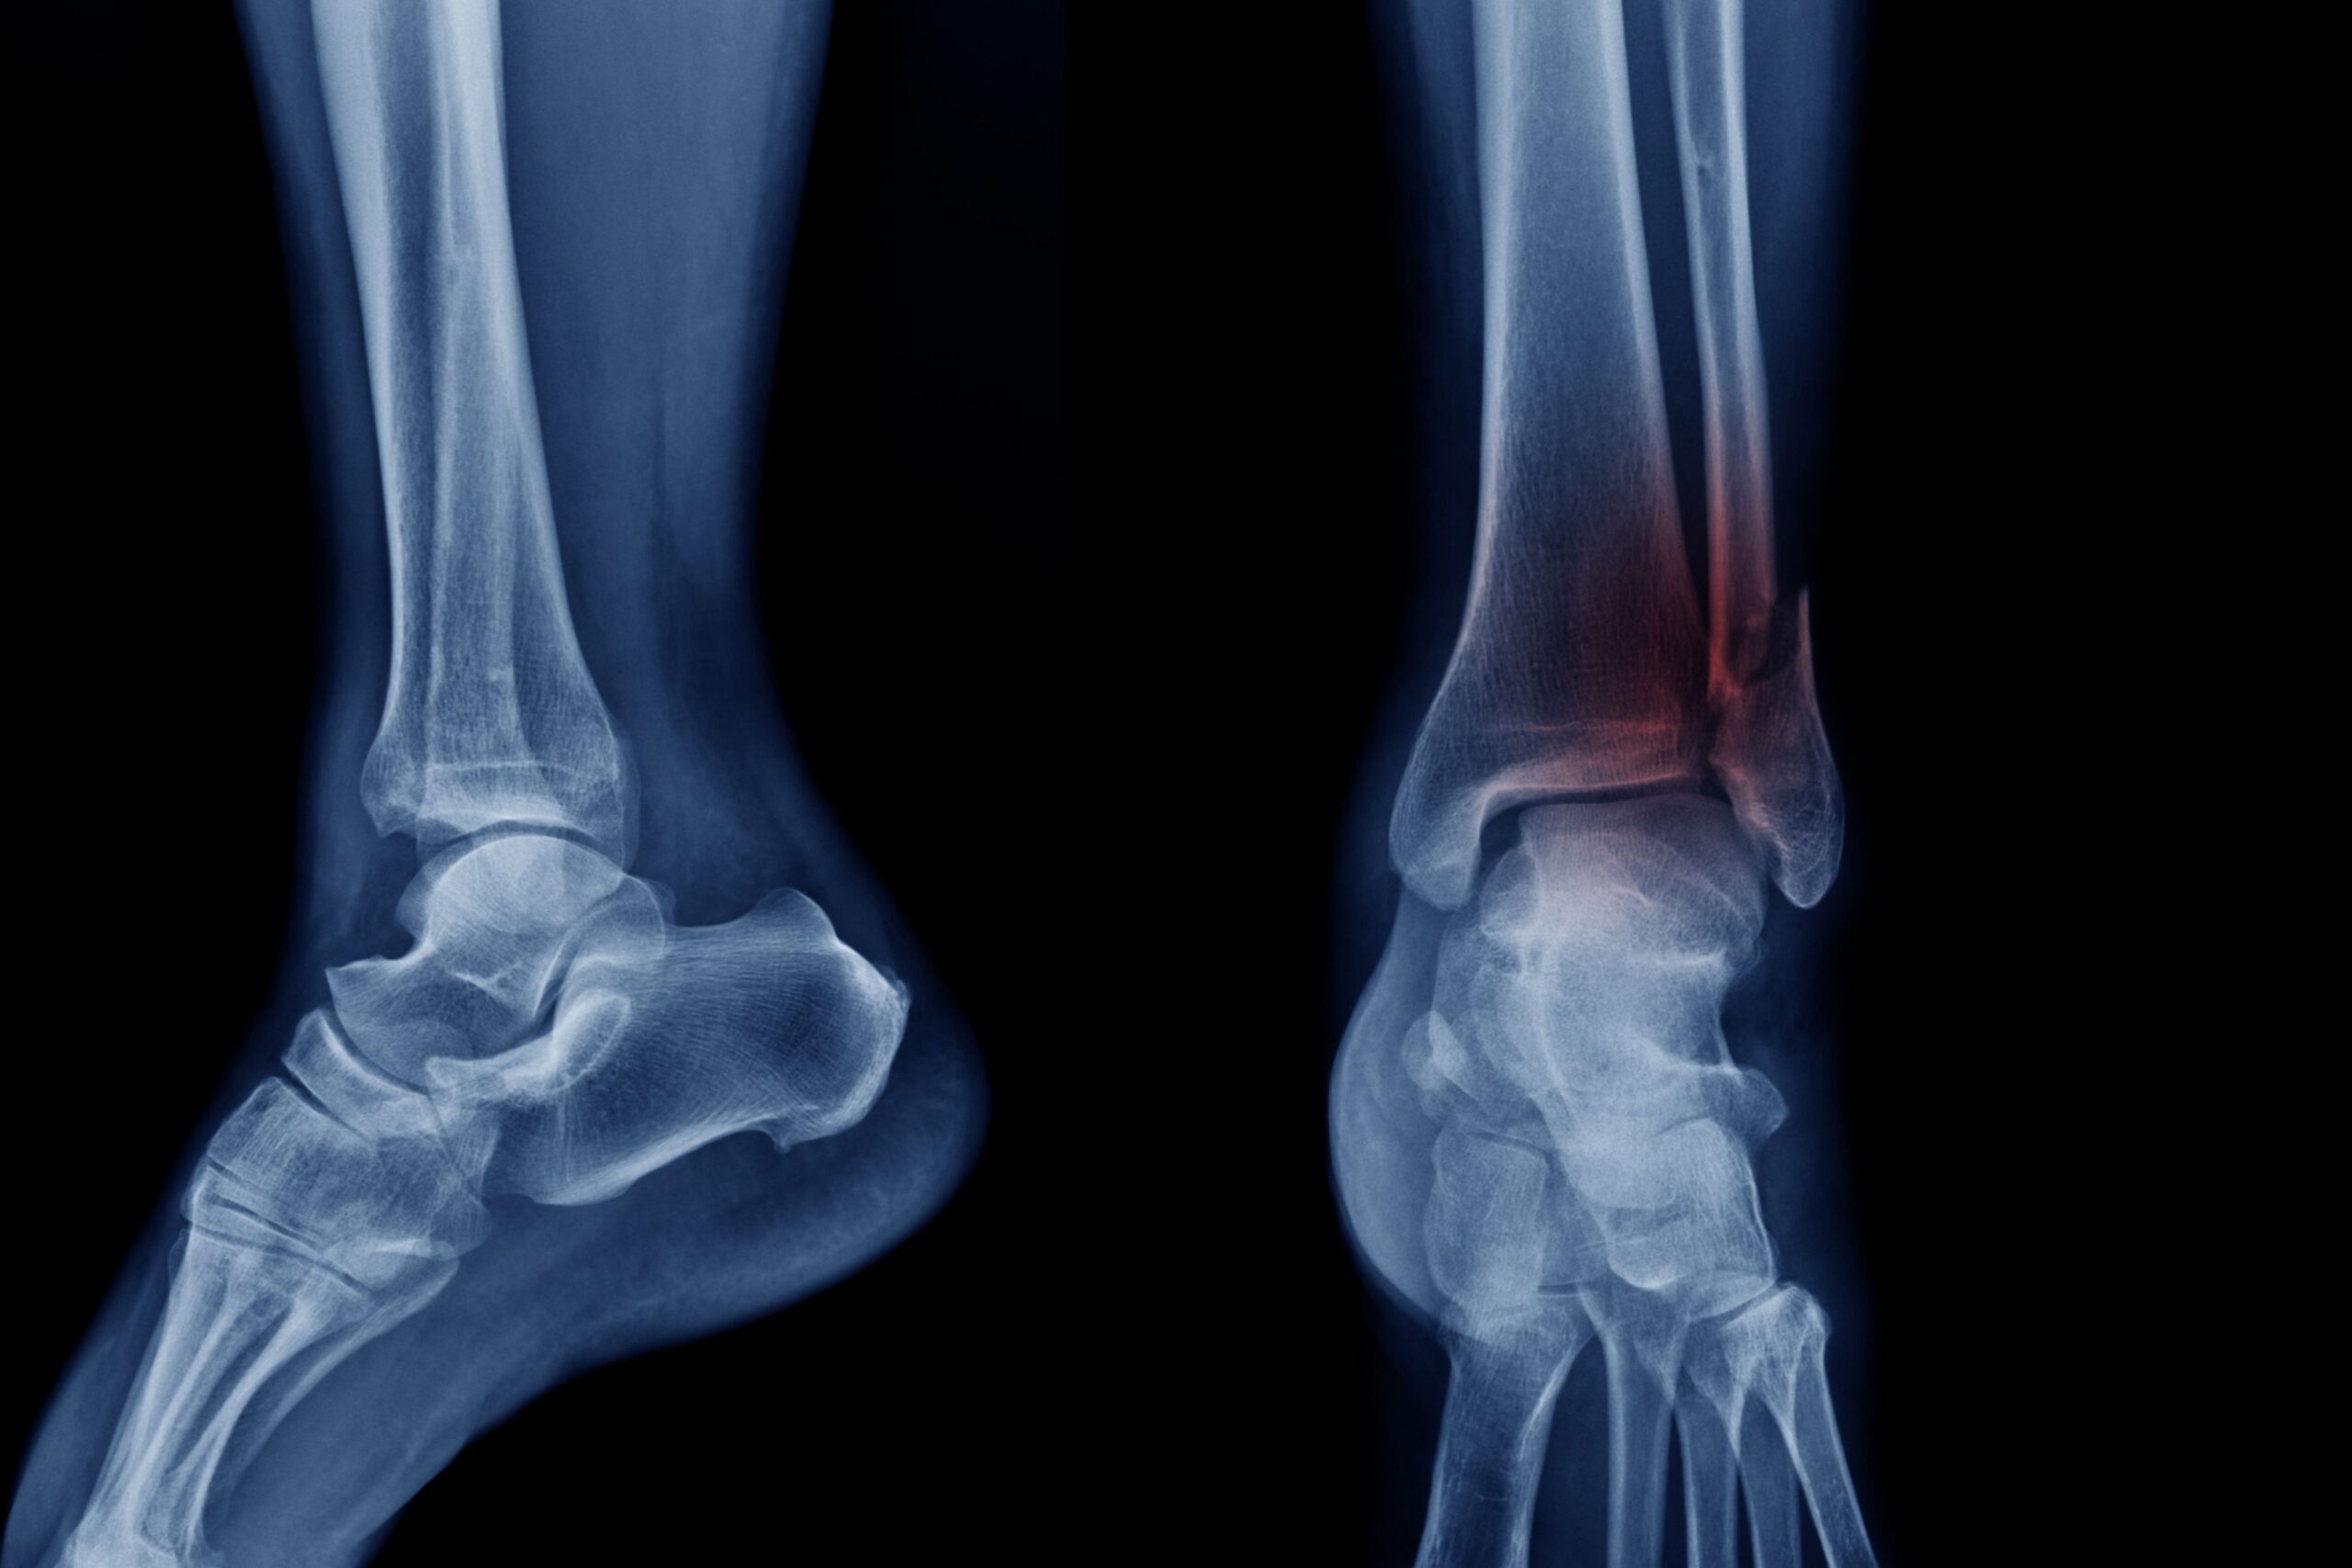

La gestione del recupero dopo un intervento di chirurgia traumatologica sta evolvendo rapidamente grazie ai protocolli Enhanced Recovery After Surgery (ERAS), sempre più utilizzati anche in ambito ortopedico. Un nuovo studio pubblicato sulla rivista Therapeutics and Clinical Risk Management evidenzia come l’applicazione di programmi riabilitativi basati su questi principi possa migliorare significativamente il recupero dopo interventi per frattura di caviglia.

La ricerca fornisce indicazioni interessanti per ortopedici, fisioterapisti e tecnici ortopedici coinvolti nella gestione post-chirurgica dei pazienti con trauma alla caviglia, una delle condizioni più frequenti nella pratica clinica ortopedica.

Le fratture di caviglia rappresentano una delle lesioni traumatiche più frequenti dell’apparato muscoloscheletrico e possono determinare instabilità articolare, dolore persistente e limitazioni funzionali. In questo scenario, protocolli riabilitativi strutturati come ERAS potrebbero avere ricadute importanti anche per il settore dell’ortopedia tecnica, in particolare per quanto riguarda la gestione precoce del carico e del cammino; l’utlizzo di tutori e dispositivi di immobilizzazione funzionale; l’integrazione tra chirurgia, fisioterapia e supporti ortopedici.